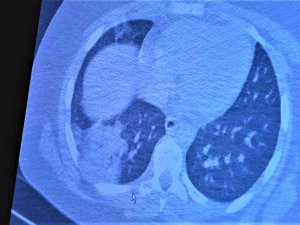

Koronaya Yakalanan 15 Yaş Altı Çocuklarda Ciddi Akciğer Tutulumları